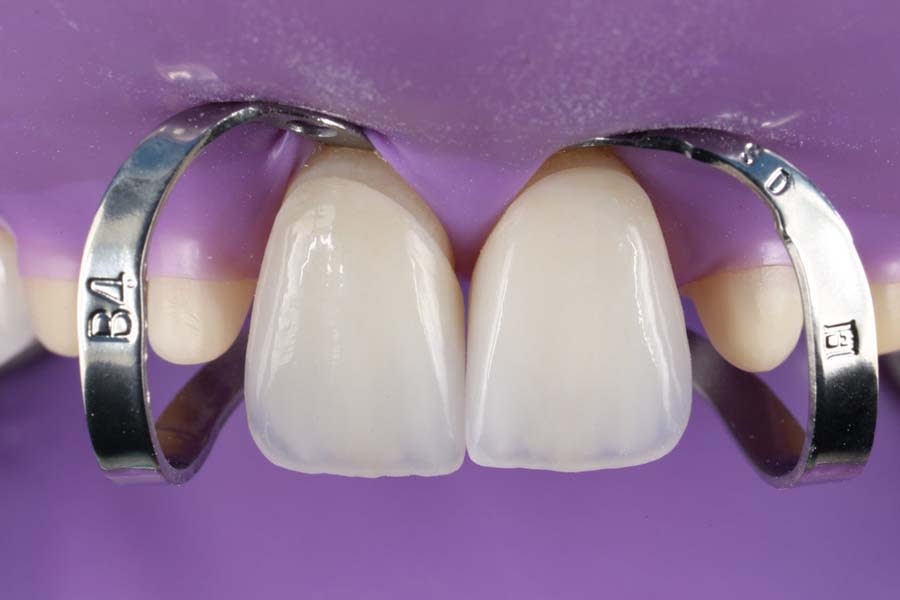

Cementation was performed under rubber dam isolation following total-etch adhesive protocols,13 which included etching of enamel and dentin, priming, adhesive application, resin cementation, excess cement removal, proximal contact verification, and occlusal adjustment. Cementation of anterior restorations is shown in Figure 13.